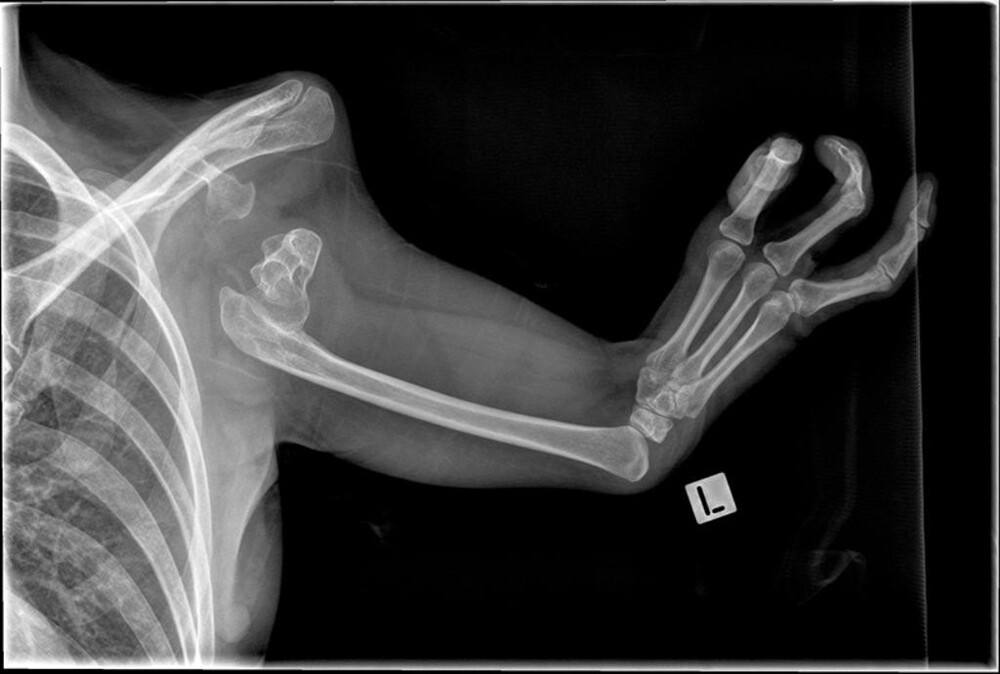

Миньон родилась в начале 1900-х годов. Вероятно, это произошло около 1910 года. Ребёнок с рождения страдал фокомелией. Фокомелия представляет собой отсутствие конечности с продолжающимся дистальным рудиментарным развитием кисти или стопы. В случае с Миньон её пальцы были сросшимися таким образом, что походили на ласты.

Рентген верхних конечностей пациента с фокомелией